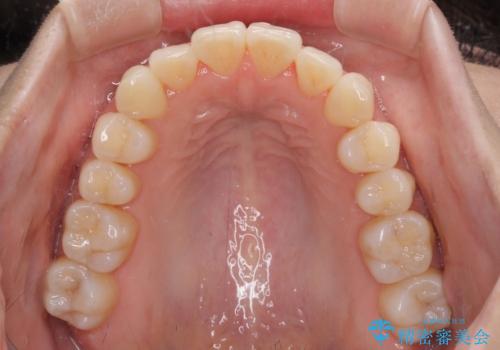

前歯のクロスバイト インビザラインによる矯正治療

- 上下のクロスバイトと前歯のデコボコを気にして来院された患者様です。

インビザラインを用い、IPR(歯と歯の間を削る)と歯列全体を拡大させることで、歯並びを整えていくこととしました。

治療を急いでいらっしゃらなかったため、のんびりと治療を進めていきました。3年以上の期間を要しましたが、きれいな口元に仕上がりました。